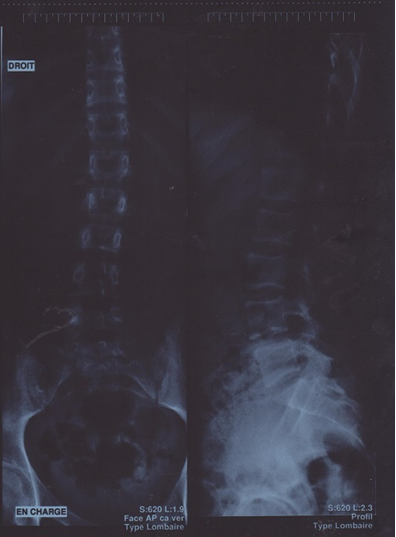

- Radiographies